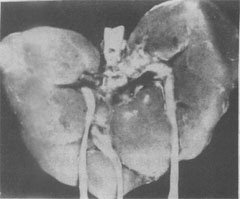

(2)Edwards综合征:染色体异常为18三体。表型特征有智力低下、小头、前额窄、枕部突、小颌且张口范围小,腭弓高窄、低位耳、肾畸形(图6-3)、肌张力增高及手紧握等(图6-4)。

图6-3 18三体(Edwards)综合征的畸形肾

图示马蹄状融合肾及额外输尿管